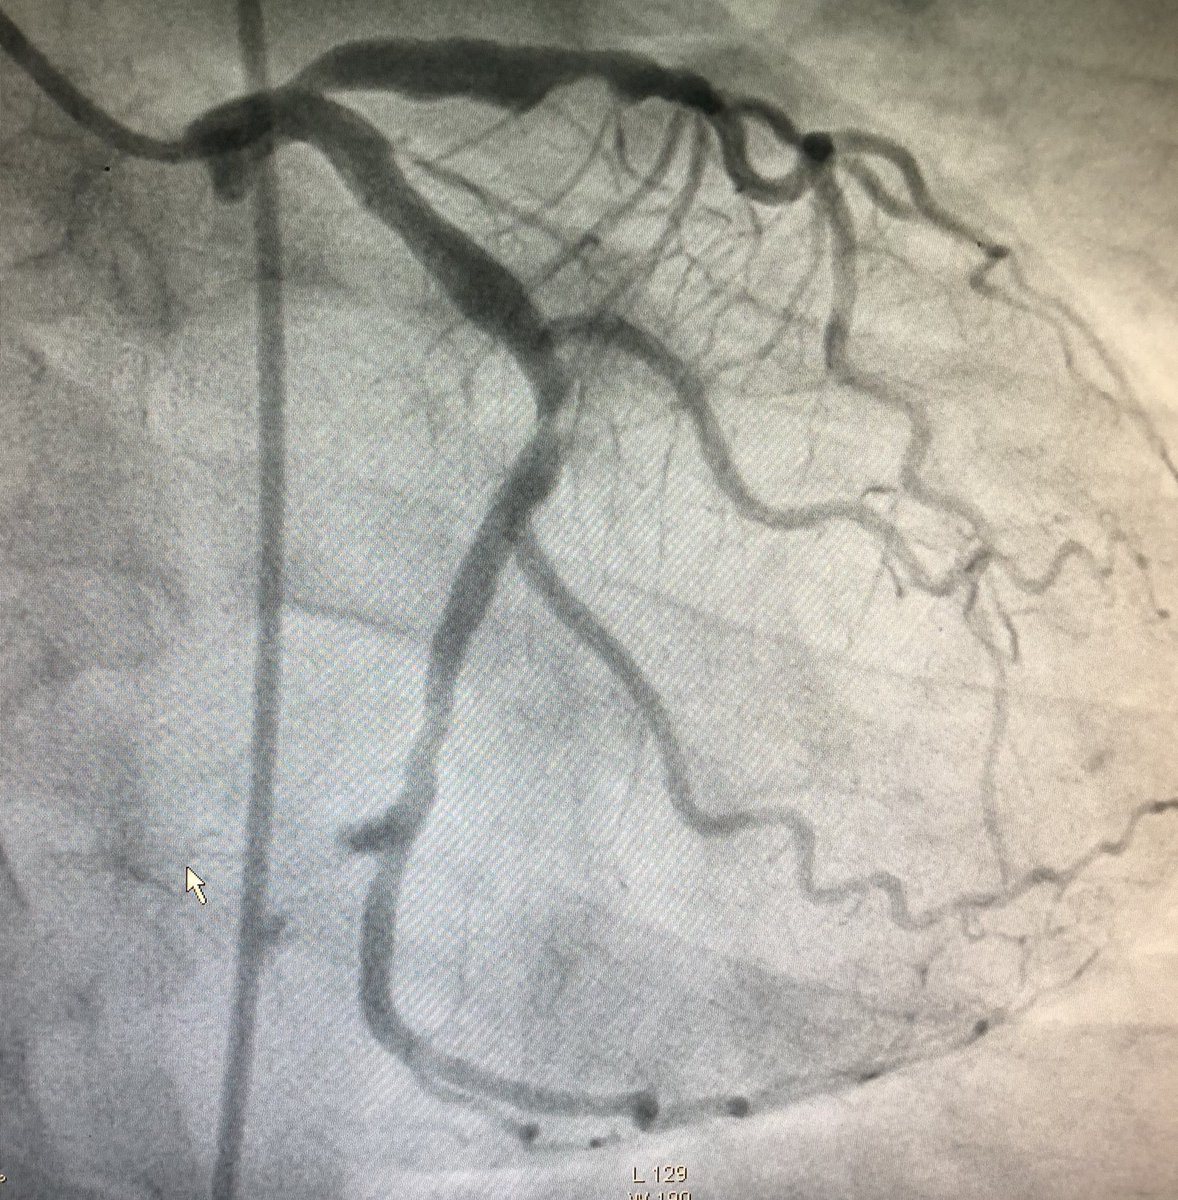

Referred for second opinion

@EuroInterventio#Bifurcations How would u treat? Ostial LAD dz and ectatic proximal segment@mmamas1973@willsuh76@sbrugaletta@jedicath@VijayKunadian@Ortega_Pazpic.twitter.com/efCyf6OKFj